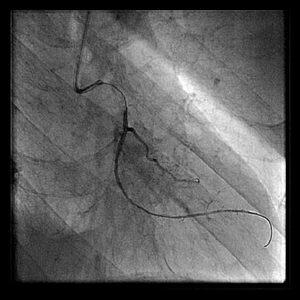

画像のPCI-1、2、3は1stPCIで1年後のAMI、resque後、stenting後となっています。

resqueでは血栓が引けたように記憶しています。